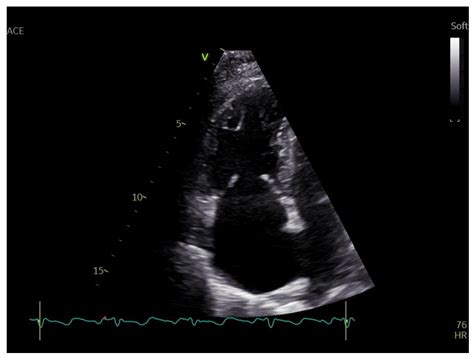

• Echocardiogram: This is the primary diagnostic tool, using ultrasound waves to create images of the heart and assess the function of the tricuspid valve.